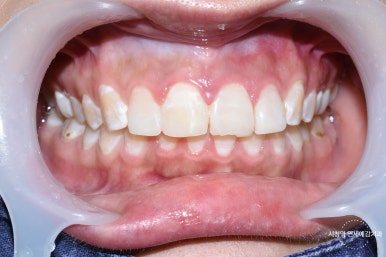

Case 3.

라미네이트가 깨져서 급하게 오신

외국인 관광객 환자분이었습니다.

라미네이트가 깨진 경우 원래는 다시 라미네이트나 크라운 등

라미네이트 이상의 치료를 하셔야하는데 출국하셔야 하는 해외환자분이라

레진으로 임시로 해드렸고 환자분께서 신세계 를 경험하셨다고 하셨습니다!